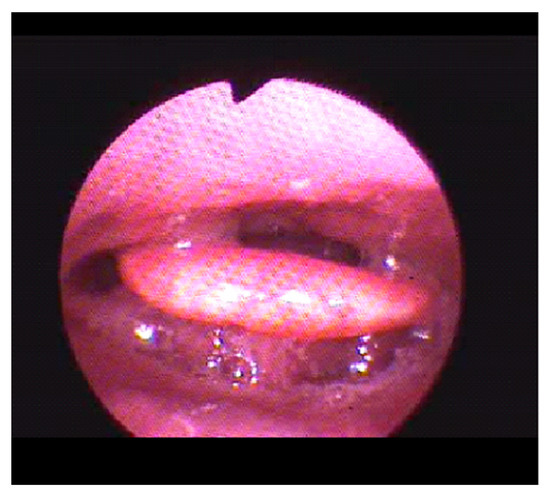

Finally, a bimanual mandibular advancement maneuver has been practiced for evaluating the degree of enlargement of the space in the sites of respiratory obstruction. With endoscopic evidence, we advanced the mandible from 4 to 5 mm by observing the positive effect on airway obstruction, snoring and oxygen saturation. The mandibular progress was then reproduced with the help of the fork: it was inserted into the mouth and the lower incisors were stuck in the groove of the lower part, which exactly reproduced their shape. Then, a front traction was performed on the fork handle, advancing the jaw until it was possible to insert the upper incisors in the groove present in the upper part, also faithfully identical to their morphology (Figure 5).

Figure 5. The bite fork positioned during DISE in patient 2.